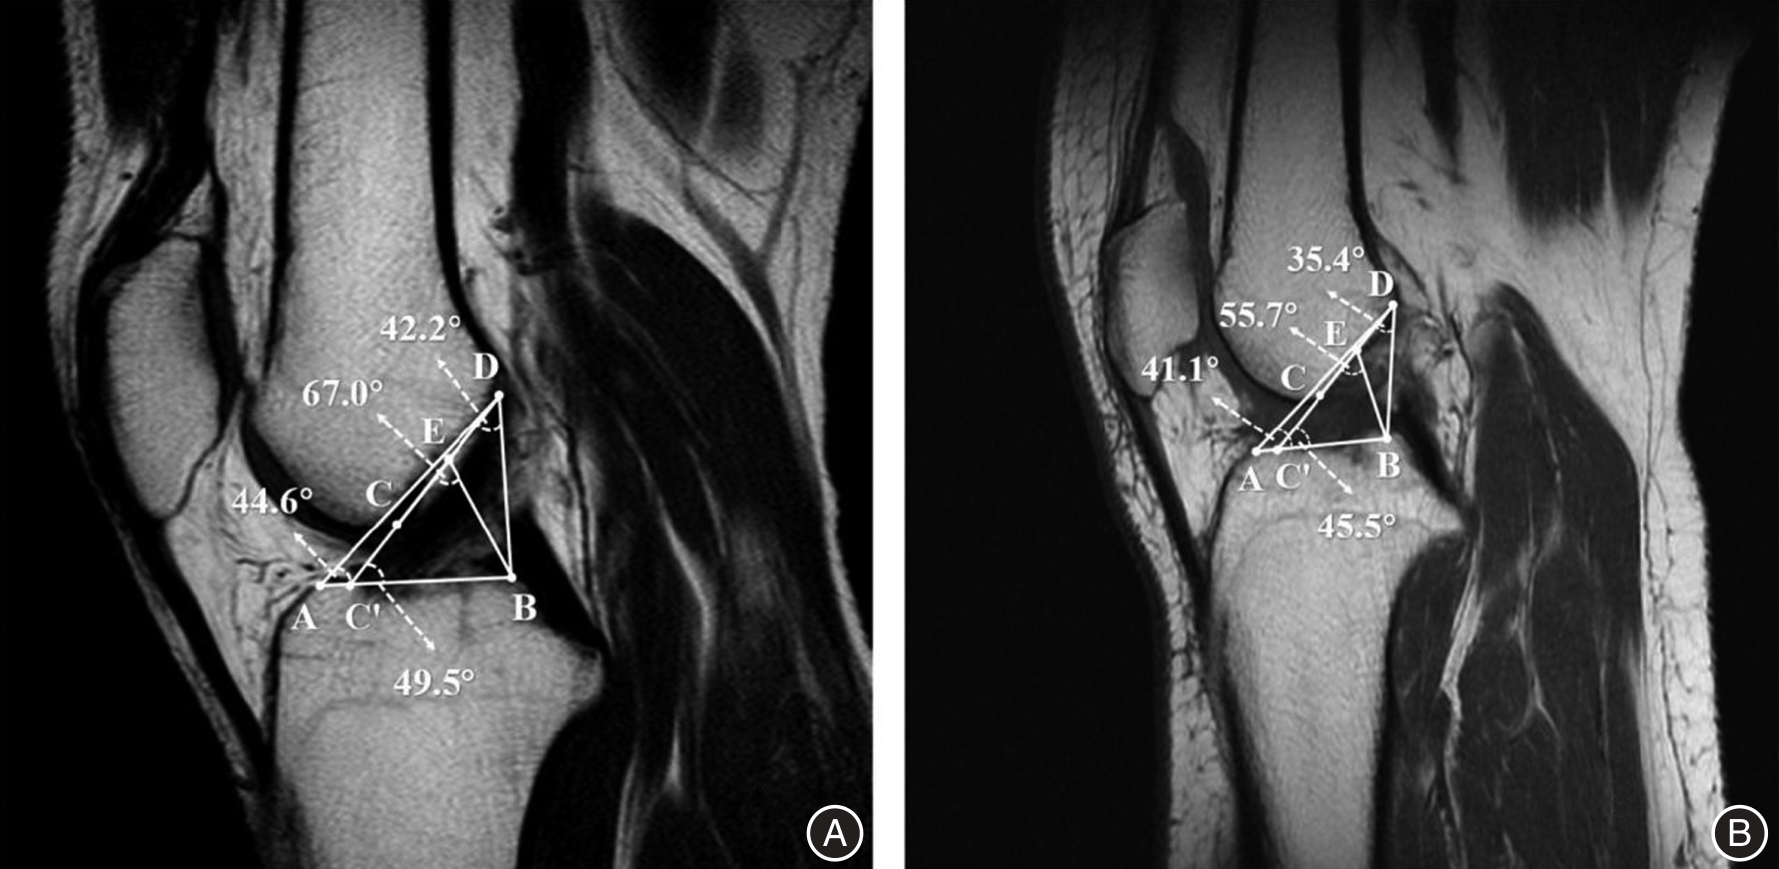

Objective To investigate whether the geometric triangular relationship between the Blumensaat line and the tibial plateau can serve as an auxiliary diagnostic index for identifying and evaluating anterior cruciate ligament (ACL) injuries, thereby enhancing diagnostic accuracy. Methods A retrospective self?controlled study was conducted involving 64 patients diagnosed with unilateral ACL injury via arthroscopy and treated with ACL reconstruction at Qingdao Municipal Hospital from January to August 2023. Ultimately, 40 cases were included in the analysis. Preoperative MRI images of the affected knees and contralateral healthy knees were collected as the ACL injury group and control group, respectively. In the MRI images, point C, point D, and point E were defined as the anterior end, posterior end, and midpoint of the Blumensaat line, respectively; point A and point B were defined as the turning points of the anterior and posterior edges of the tibial plateau, respectively; and point C' was defined as the intersection of the extension line of DC and line AB. Based on these anatomical landmarks, angles ∠DAB, ∠CEB, ∠DC'B, and ∠CDB were established. The intra?class correlation coefficient (ICC) was calculated to assess measurement consistency and reproducibility. Differences between the aforementioned angles were compared, and the area under the receiver operating characteristic (ROC) curve was computed to evaluate diagnostic performance. Results For ∠CDB, ∠DC'B, ∠CEB, and ∠DAB, the intra?group and inter?group correlation coefficients all exceeded 0.80, indicating excellent consistency and reproducibility. Compared to the control group, the angles ∠CDB, ∠CEB, and ∠DAB in the ACL injury group were significantly reduced (P < 0.001). Among these, ∠DAB appears to be the most reliable index for diagnosing and evaluating ACL injuries, with an area under the receiver operating characteristic curve (AUC) of 0.829, a cut?off value of 42.2°, a sensitivity of 82.5%, and a specificity of 80.0%. Conclusion The geometric triangular relationship between the Blumensaat line and the tibial plateau in MRI images, particularly the angle ∠DAB, can serve as an auxiliary indicator for diagnosing and evaluating ACL injuries, thereby enhancing diagnostic accuracy.